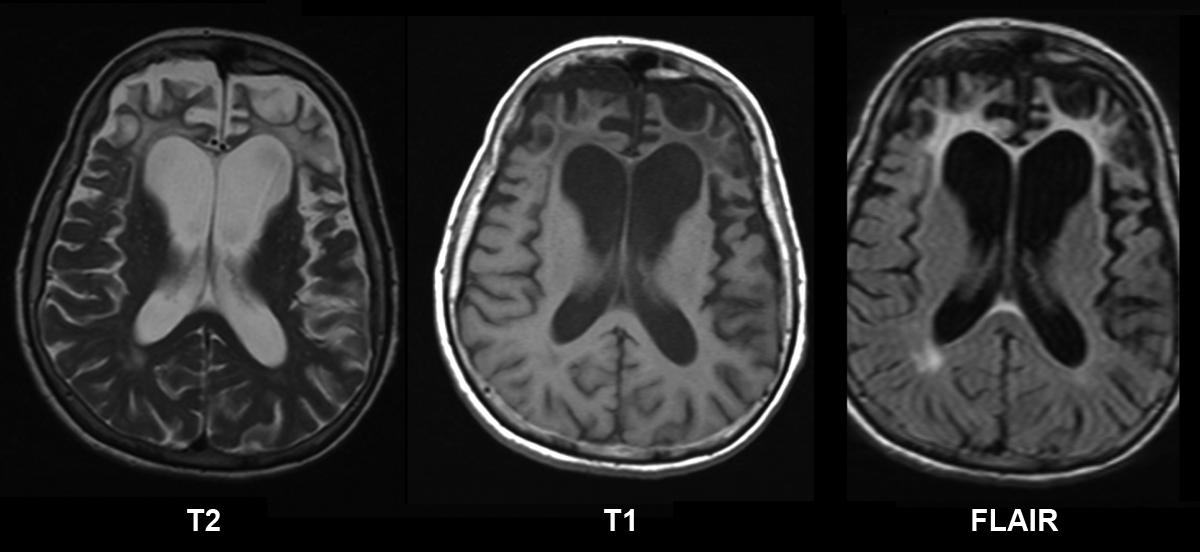

English: Brain MRI of a female 65 y.o. white patient with Pick's disease. Cortex and white matter atrophy of the frontal lobes is clearly visible. The MRI was done without contrast enhancement utilizing Magnetom Vision 1.5 Tesla with superconductive magnet.